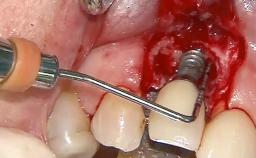

Surgical Management of Peri-Implantitis: Removal of Implant Due to Recurrent Infection Using an Implant-Retrieval Tool

Despite anti-infective surgical treatment, some patients may experience recurrent infection and progressive bone loss requiring additional treatment. This case describes a conservative approach using an implant retrieval tool without the need for excessive bone removal or use of a trephine.